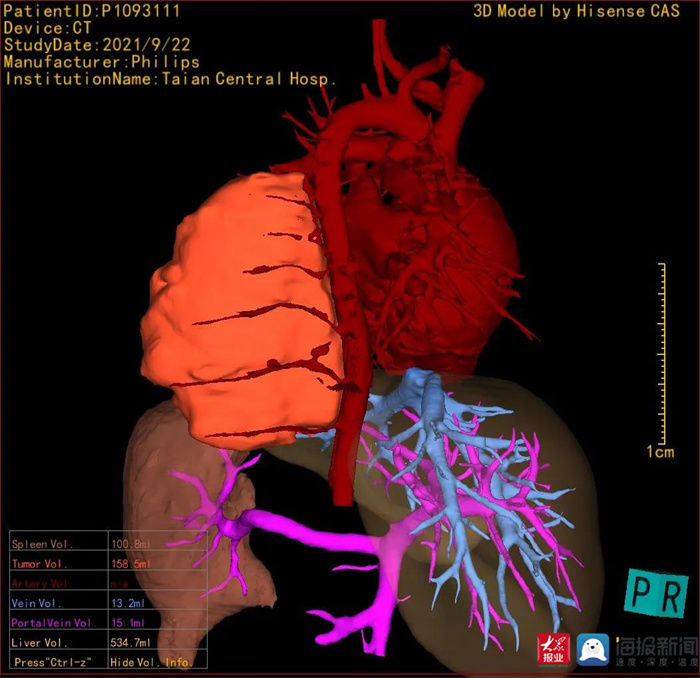

CAS检查(李庆浩 供图)

海信计算机辅助手术系统(CAS)的应用成功解决了这个问题。术前,儿童外科团队借助CAS系统评估发现,患儿的肿瘤体积高达162.1ml,肉眼看竟然比心脏的体积还大。最终,在CAS的导航下,在医院麻醉科、手术室及儿童外科其他医师的密切配合和共同努力下,由儿童外科主任李庆浩主刀,成功为患儿施行了胸腔镜下纵膈肿瘤切除术,整个手术过程中没有输血,手术出血量仅仅10ml,手术创面无明显出血,手术实现了精准微创。术后,患儿恢复良好,目前身体各项指标均无明显异常。

李庆浩介绍,肿瘤细胞不断地生长、繁殖,挤压甚至侵袭周围的正常器官组织中,该怎样手术?该切除哪里?外科医生以往需要借助二维影像“片子”来想象,在脑海中模拟患者病处的情况。现在,海信计算机辅助手术系统(CAS)可以对二维影像进行三维重建,并把三维模型呈现在大屏幕上,让大家一目了然,更有针对性地解决问题。